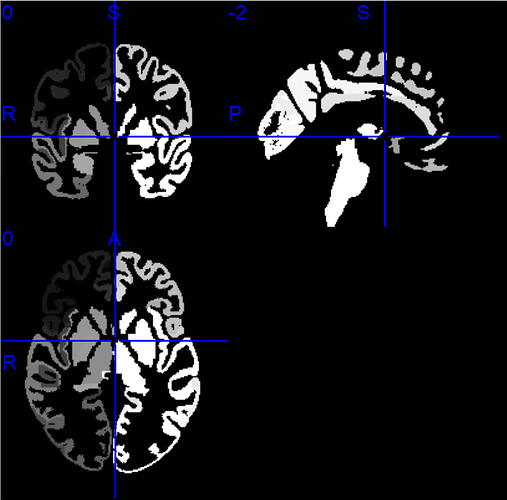

老师您好,我也是想把DK图谱的脑区映射到Yeo 7子网络中,您推荐的这个项目中,给了很多图谱文件,Yeo 7图谱应该是Yeo-7_space-MNI152NLin6_res-1x1x1.nii.gz这个文件,但我不知道常用的DK图谱(包含68个脑区的)是哪一个,烦请老师指教。文件夹中有Desikan_space-MNI152NLin6_res-1x1x1.nii.gz、DesikanKlein_space-MNI152NLin6_res-1x1x1.nii.gz和DKT_space-MNI152NLin6_res-1x1x1.nii.gz三个文件,在MRIcron中打开分别如下:

-